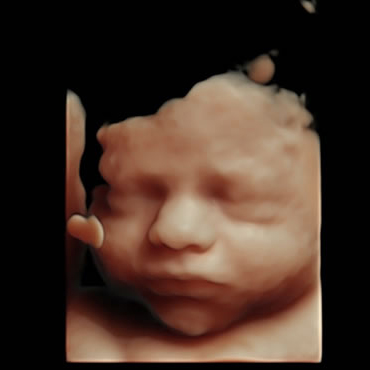

• 3D/4D-Ultraschall

Räumliche Darstellung der kindlichen Körperteile in Echtzeit.